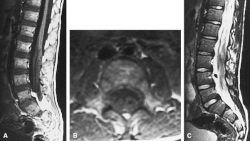

| MRI compatible with Dejerine-Sottas type spinal nerve enlargement | |

On medical imaging, the peripheral and cranial nerves are enlarged by redundant connective tissue. On histology, this enlargement gives the nerves the appearance of an onion-bulb. Nerve excitability and conduction speed are reduced.[1]